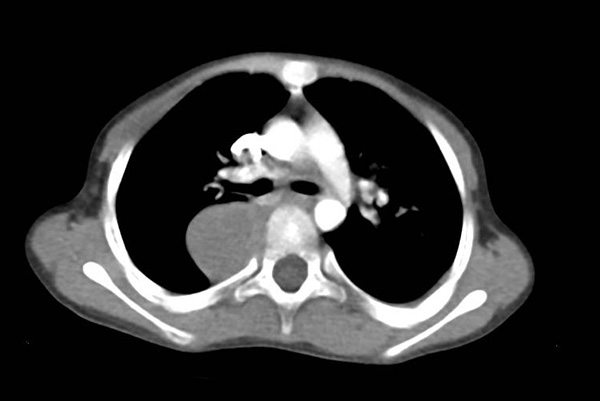

与成人纵隔肿瘤的来源不同,儿童的纵隔肿瘤更多的以胚胎来源为主,且恶性的可能性也更大。根据肿瘤发病位置不同,常见的肿瘤类型也不尽相同。儿童前纵隔肿瘤以淋巴瘤和畸胎瘤为主,发生在后纵隔的肿瘤则更常见是神经源性肿瘤,后者也是儿童发病率较高的实体肿瘤之一。

因为纵隔位置的特殊性,肿瘤刚刚形成的早期可能没有任何症状,因此很多患儿来就诊时往往是因为胸部影像学检查或体检时无意中发现的。随着肿瘤体积的逐渐增大,可能会带来一些继发症状,通常是肿瘤太大压迫到周围的器官导致的。比如压迫到气管可能会出现呼吸困难,压迫食管则导致吞咽困难,压迫到大血管可能会使血液回流受限而出现面部的水肿。

一般来讲,大部分患儿通过一张简单的胸片多能看到不同于正常的纵隔占位。如果发现患儿有相应的症状或检查发现纵隔存在异常占位,需要家长们及时带患儿至医院就诊,进一步完善影像学检查明确肿瘤的情况,手术切除或是取病理进行活检则是确定肿瘤性质的金标准。